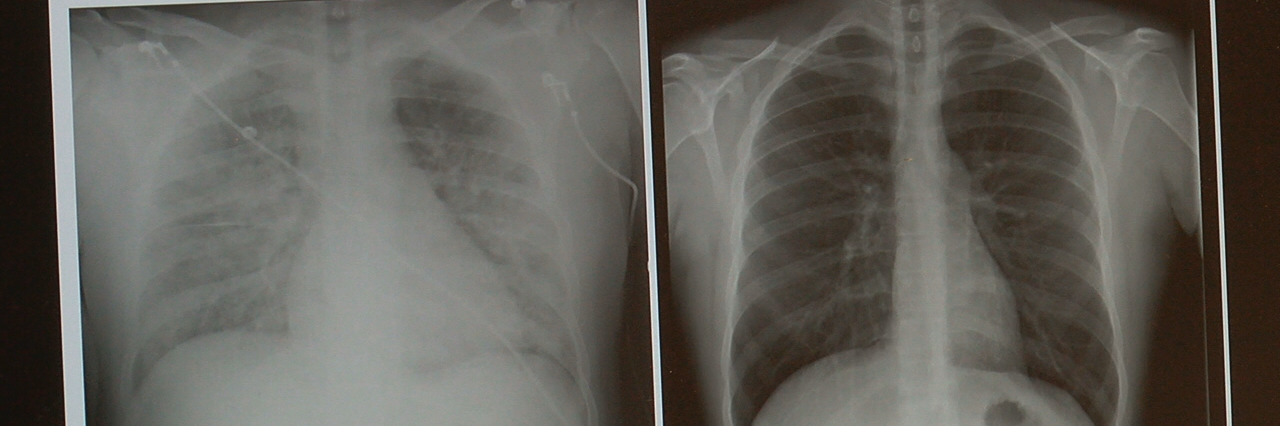

You can have a pseudomediastinum

We don’t want to bombard you with science, but if you hold in a sneeze, you might potentially experience a pseudomediastinum. This is what happens when air gets trapped between your lungs, which can cause major problems. If you suspect this might have happened after you’ve held in a sneeze, seek medical attention as quick as you can.Advertisement